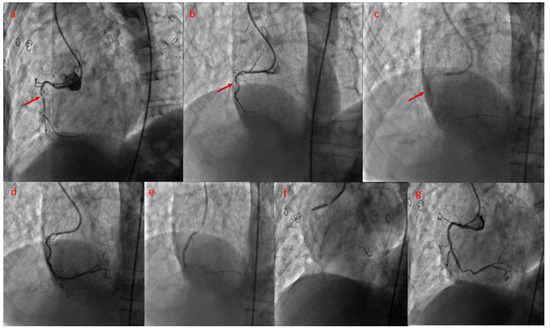

Excimer Laser Coronary Atherectomy: Current Evidence, Clinical Applications, and Future Directions

by Mohsen Mohandes, Alberto Pernigotti, Mauricio Torres, Cristina Moreno Ambroj, Francisco Fernández, Roberto Bejarano-Arosemena, Pablo Moreno, Anna Vidal-Romero, Jordi Guarinos and Jose Luis Ferreiro

J. Clin. Med. 2026, 15(2), 766; https://doi.org/10.3390/jcm15020766 - 17 Jan 2026

Viewed by 181

Abstract

Excimer Laser Coronary Atherectomy (ELCA) has re-emerged as a valuable adjunctive modality in percutaneous coronary intervention (PCI), particularly in the context of increasingly complex coronary anatomy and rising procedural expectations. By delivering pulsed ultraviolet energy at 308 nm through flexible fiber-optic catheters, ELCA [...] Read more.

Excimer Laser Coronary Atherectomy (ELCA) has re-emerged as a valuable adjunctive modality in percutaneous coronary intervention (PCI), particularly in the context of increasingly complex coronary anatomy and rising procedural expectations. By delivering pulsed ultraviolet energy at 308 nm through flexible fiber-optic catheters, ELCA enables precise photochemical, photothermal, and photomechanical ablation of atherosclerotic, fibrotic, calcified, and thrombotic tissue while minimizing thermal injury to surrounding structures. Recent technical refinements, simplified catheter designs, and improved safety profiles have enhanced its feasibility and utility across a range of challenging lesion subsets. This review summarizes the fundamental principles underlying excimer laser–tissue interaction, discusses available equipment and key procedural considerations, and examines the expanding clinical evidence supporting ELCA in contemporary practice. Data from observational studies and multicenter registries suggest that ELCA may enhance device crossability, restore coronary flow, and reduce distal embolization in thrombus-rich lesions, particularly during primary PCI. In device-uncrossable lesions, ELCA facilitates plaque modification and improves procedural success, including in chronic total occlusions. Furthermore, ELCA—especially when performed with simultaneous contrast injection—has demonstrated efficacy in treating stent underexpansion refractory to high-pressure balloon dilation, improving minimal stent area and enabling optimal post-dilatation. As lesion complexity continues to increase, ELCA is gaining recognition as an important tool within the interventional armamentarium. While generally safe in experienced hands, ELCA carries a risk of procedural complications that must be carefully considered. Ongoing investigations are expected to further define its optimal use and reinforce its relevance in modern interventional cardiology. Full article

Show Figures

Figure 1